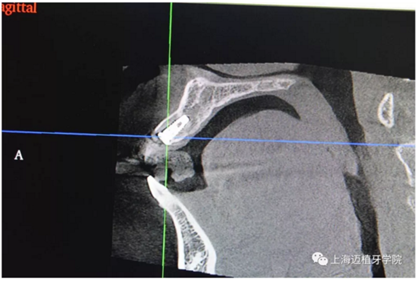

主訴:前門外傷牙根折要求修復?現(xiàn)病史:前門牙外傷,劈裂至根部,無法固定及其他修復,要求種植?檢查:11牙冠2/3缺損,唇腭向劈裂,唇部紅腫。 CT示根折, 骨寬度9.47mm,距鼻底12.34mm,Ⅲ類骨。 口腔衛(wèi)生一般

CR片